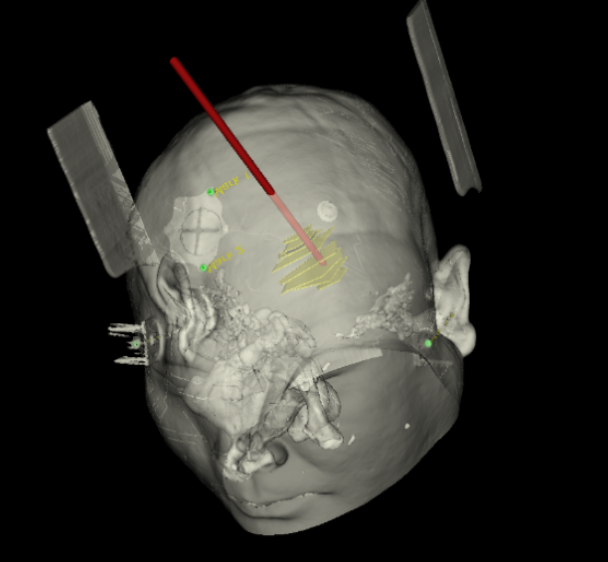

術(shù)前韓帥醫(yī)生使用“睿米”制定手術(shù)規(guī)劃

手術(shù)規(guī)劃在機器人軟件上制定完成